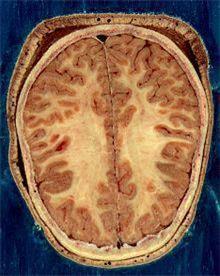

뇌는 신경 세포체로 구성돼 입력된 정보를 처리하는 겉 부분인 대뇌 피질과 신경세포들을 서로 연결하는 신경 섬유망이 깔려 서로 다른 뇌 부위들을 연결하는 속 부분인 수질로 이루어져 있다. 피질은 회색을 띠고 있어 회색질, 수질은 하얀색을 띠고 있어 백질이라고 불린다.

전체적으로 중강도 내지 고강도 운동(달리기, 걷기, 스포츠 등)을 규칙적으로 하는 사람은 다른 사람보다 뇌의 회색질과 백질의 용적이 큰 것으로 나타났다고 연구팀은 밝혔다.

중강도·고강도 운동 일수가 많을수록 회색질, 백질, 해마, 전두엽, 두정엽, 후두엽의 용적은 커졌다.